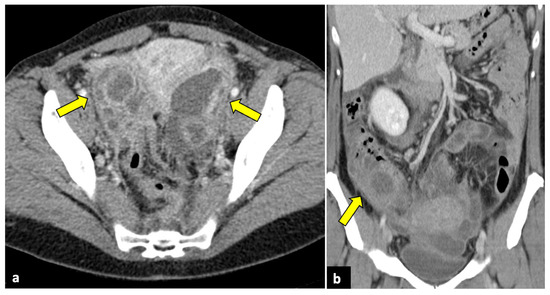

Gynaecological Causes of Acute Pelvic Pain: Common and Not-So-Common Imaging Findings

by Paolo Niccolò Franco, Alejandra García-Baizán, María Aymerich, Cesare Maino, Sofia Frade-Santos, Davide Ippolito and Milagros Otero-García

Life 2023, 13(10), 2025; https://doi.org/10.3390/life13102025 - 9 Oct 2023

In female patients, acute pelvic pain can be caused by gynaecological, gastrointestinal, and urinary tract pathologies. Due to the variety of diagnostic possibilities, the correct assessment of these patients may be challenging. The most frequent gynaecological causes of acute pelvic pain in non-pregnant [...] Read more.

In female patients, acute pelvic pain can be caused by gynaecological, gastrointestinal, and urinary tract pathologies. Due to the variety of diagnostic possibilities, the correct assessment of these patients may be challenging. The most frequent gynaecological causes of acute pelvic pain in non-pregnant women are pelvic inflammatory disease, ruptured ovarian cysts, ovarian torsion, and degeneration or torsion of uterine leiomyomas. On the other hand, spontaneous abortion, ectopic pregnancy, and placental disorders are the most frequent gynaecological entities to cause acute pelvic pain in pregnant patients. Ultrasound (US) is usually the first-line diagnostic technique because of its sensitivity across most common aetiologies and its lack of radiation exposure. Computed tomography (CT) may be performed if ultrasound findings are equivocal or if a gynaecologic disease is not initially suspected. Magnetic resonance imaging (MRI) is an extremely useful second-line technique for further characterisation after US or CT. This pictorial review aims to review the spectrum of gynaecological entities that may manifest as acute pelvic pain in the emergency department and to describe the imaging findings of these gynaecological conditions obtained with different imaging techniques. Full article

Show Figures

Figure 1